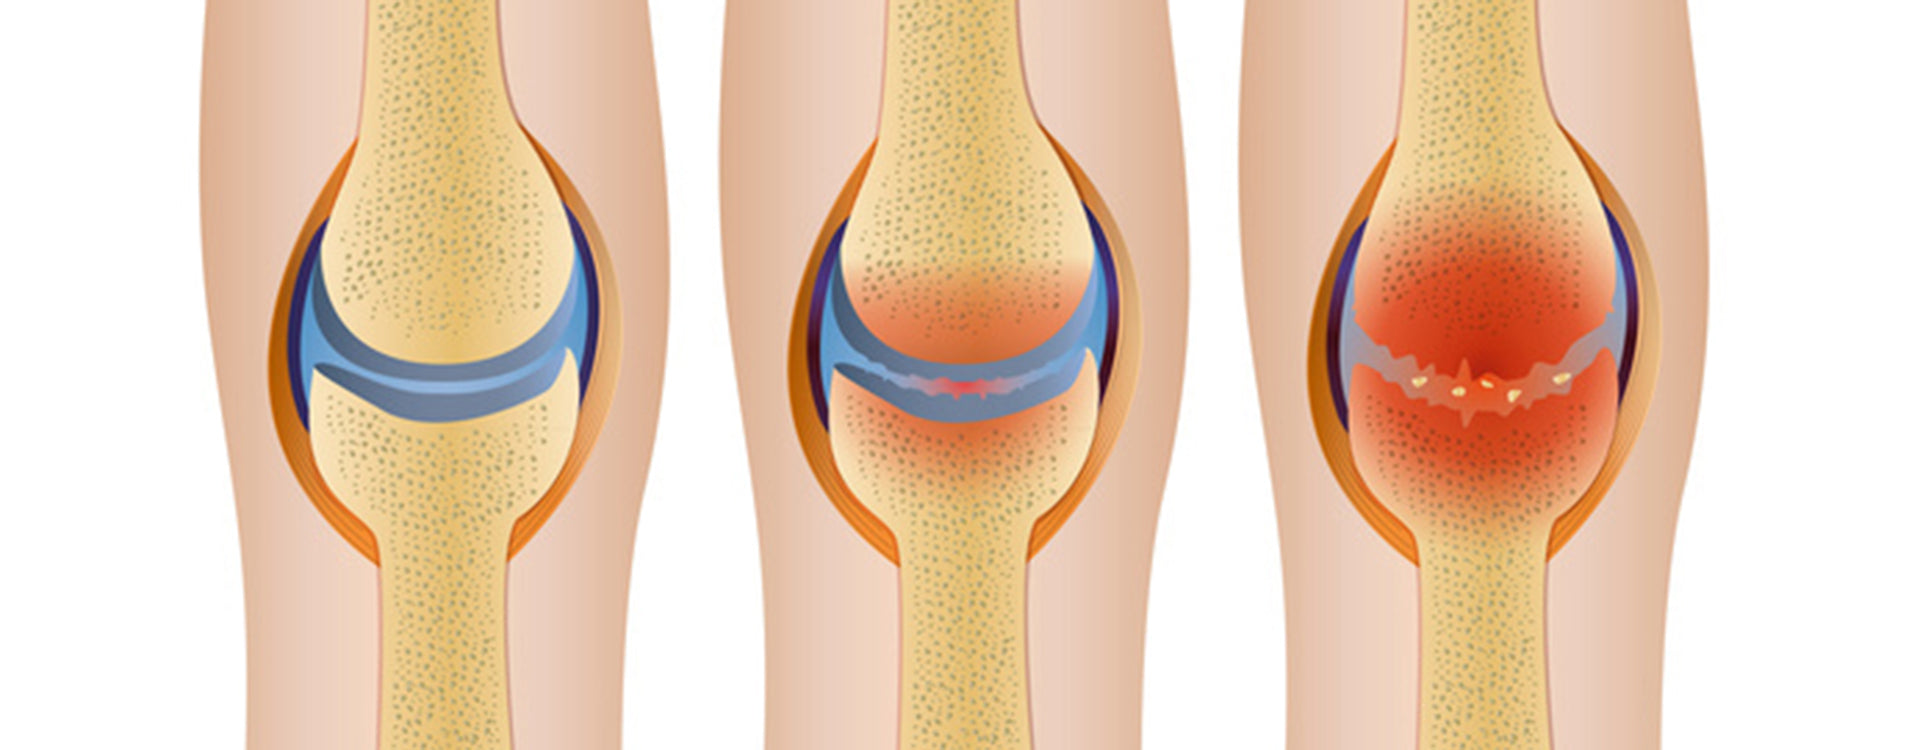

Freie Radikale fördern Zellschäden und Entzündungen („oxidativer Stress“) – ein Treiber degenerativer Gelenkerkrankungen. Antioxidantien aus Pflanzenkost (z. B. Vit. C/E, sekundäre Pflanzenstoffe) neutralisieren Radikale.

Zu wenig Bewegung macht Knorpel rau und brüchig – das Arthroserisiko steigt. Früh aktiv werden, moderat & regelmäßig trainieren, um Verlauf zu bremsen.